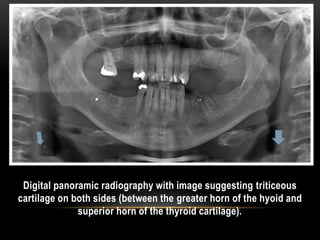

Digital panoramic radiography with image suggesting triticeous

cartilage on both sides (between the greater horn of the hyoid and

superior horn of the thyroid cartilage).